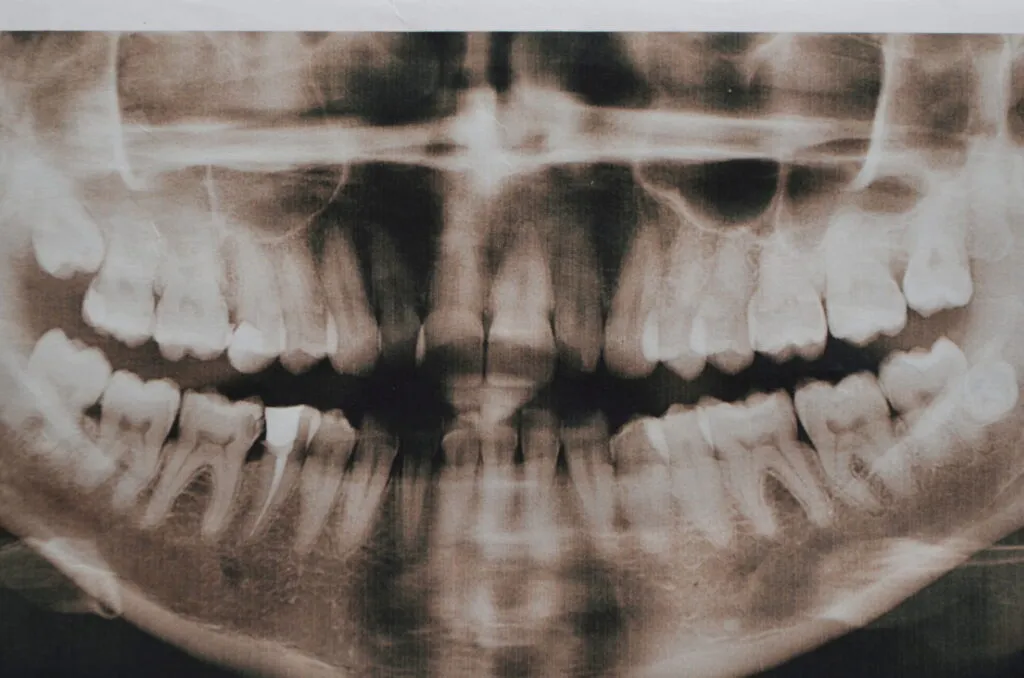

11. Hyperdontia

Hyperdontia is a rare condition that causes a person to grow extra teeth, which can look like bumps on the roof of the mouth. Extra teeth don’t typically cause symptoms, but some people may experience pain.

Doctors aren’t sure what causes hyperdontia, but it probably develops due to environmental and genetic factors.

Impacted teeth, such as the canines, that are having a hard time erupting can also cause bumps on the roof of the mouth.

Treatment

A dentist or an oral surgeon can remove the extra teeth if they crowd or displace the other teeth or dental appliances.

Impacted teeth can be guided into the correct position with a combination of orthodontics and surgery.